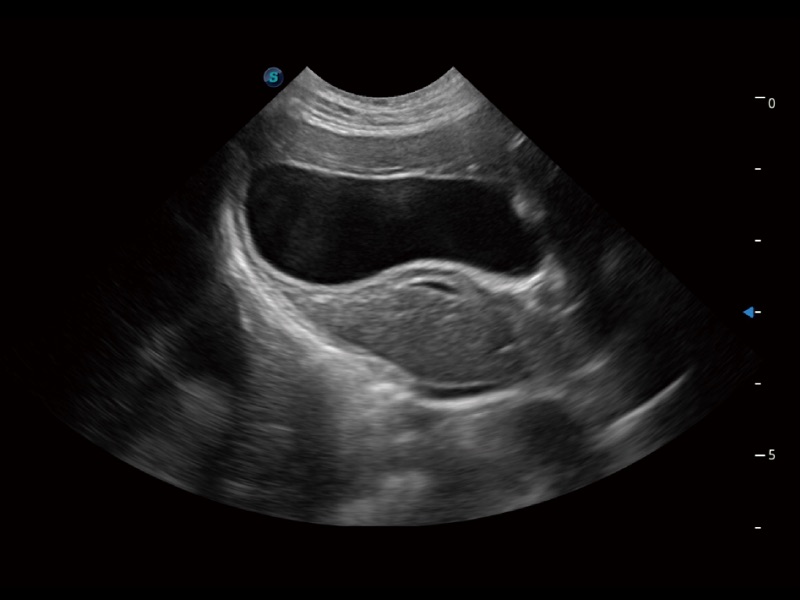

ProPet 70 进一步提升了微米成像算法,更加注重对基础原始图像的还原和保留,在有效减少斑点噪声、增强组织边界显示的同时,避免过度优化丟失真实的解剖信息。

ProPet 70专为动物医生设计,对不同的动物体型和生理结构作出了针对性的优化。通过动物影像专用软件,可满足个性化的应用需求,帮助动物医生获得更精确的诊断数据。

ProPet 70 全新的动物超声智能软件和丰富的探头群,为动物医生提供了高清晰度和精细分辨率的图像,无论在宠物、马科、畜牧还是实验室动物等应用中都可以轻松应对,为您的日常工作带来满意的体验。